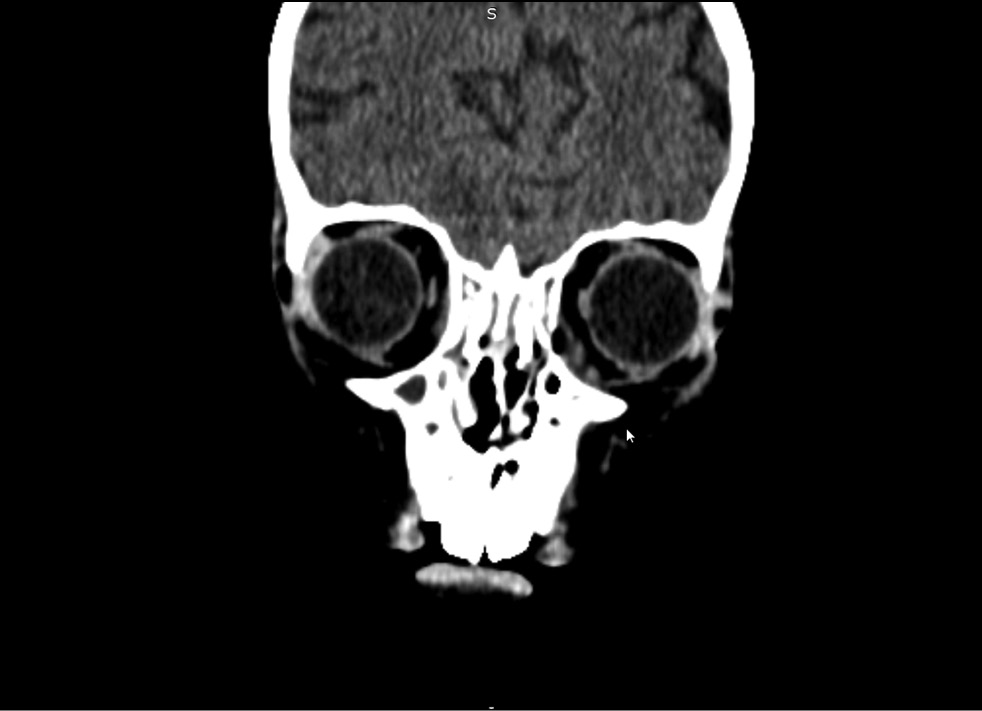

Клинические проявления риноорбитального мукормикоза появились на 6-й день госпитализации в виде отёка нижнего века слева. При этом был установлен абсцесс нижнего века. Назначена местная противовоспалительная терапия. Системно пациент получал тигециклин (1,2 мг/ кг), метронидазол, каспофунгин (70 мг/м2). Однако назначенная терапия не привела к положительной динамике заболевания, в связи с чем на 9-й день госпитализации проведена рентгеновская компьютерная томография (РКТ) орбит, придаточных пазух носа (ППН), головного мозга. Обнаружено патологическое содержимое вдоль нижнемедиальной поверхности левой орбиты с участком истончения медиальной стенки на этом уровне (воспалительные изменения), кости носа не изменены (рис. 1).

Рис. 1. Рентгеновская компьютерная томография орбит, придаточных пазух носа, головного мозга на 9-й день госпитализации.

Fig. 1. X-ray computed tomography of the orbits, paranasal sinuses, and brain on the day 9 of hospitalization.

Обнаруживалось патологическое содержимое вдоль нижнемедиальной поверхности левой орбиты с участком истончения медиальной стенки. При этом клинически были только признаки абсцесса нижнего века, в связи с чем принято решение о хирургическом лечении абсцесса. Хирургическое лечение сразу после выявления патологического процесса в орбите не проведено из-за высокого риска анестезии на фоне респираторного и инфекционно-токсического синдрома. Состояние ребёнка динамически ухудшалось с прогрессированием местной воспалительной реакции в области нижнего века.

Отмечалось молниеносное развитие некротических изменений мягких и костных тканей риноорбитальной области с 9-го по 20-й день госпитализации. На 9-й день на рентгеновской компьютерной томограмме обнаружено только истончение медиальной стенки левой орбиты. На 20-й день выявлены множественные очаги деструкции костей орбит и придаточных пазух носа. Даже небольшое промедление в проведении хирургического лечения и отказ от проведения некрэктомии, связанные с прогрессивно ухудшающимся общим состоянием ребёнка и высоким риском анестезии на фоне респираторного и инфекционно-токсического синдрома, сыграли роковую роль в судьбе пациента.